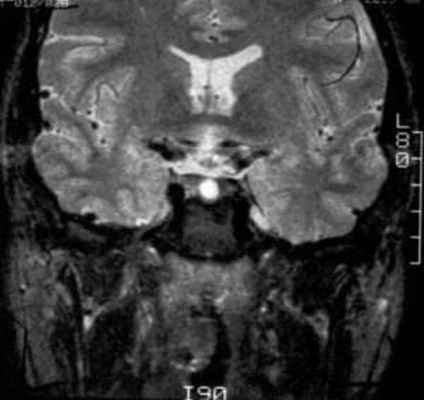

В ходе лабораторного обследования показатели общего анализа крови и мочи в пределах референсных значений, отмечено некоторое снижение протромбинового времени до 9,4 сек (10–14), повышение протромбина до 169% (70–130), общего холестерина до 5,87 ммоль/л (3,3–5,2). В гормональном анализе крови на фоне приема каберголина в дозе 0,25 мг в неделю – уровень пролактина 932,8 мЕд/л (90–540). По данным МР-томографии головного мозга в хиазмально-селлярной области подтверждено наличие объемного образования размерами 12*15*15 мм с выраженным кистозным компонентом и супраселлярным распространением (хиазма интактна). Учитывая ряд специфических признаков, специалистами отделения магнитно-резонансной томографии верифицирована киста кармана Ратке (рис. 2).

Рис. 2. Динамика объемного образования гипоталамо-гипофизарной области (А, Б – 2009 г., В, Г – 2011 г., Д, Е – 2015 г.).

На изображениях ниже можно посмотреть, как киста Ратке выглядит на снимке .

МРТ: киста кармана Ратке. На Т1-взвешенном сагиттальном изображении, полученном до введения контраста, заметно четко очерченное образование в области турецкого седла – с распространением в супраселлярную цистерну. Отмечается гомогенно высокая интенсивность сигнала в образовании по сравнению с паренхимой головного мозга.

Т2-взвешенное аксиальное изображение (тот же пациент, что и на предыдущем изображении).

Т2-взвешенное аксиальное изображение: изоинтенсивное коре образование (тот же пациент, что и на предыдущем изображении).